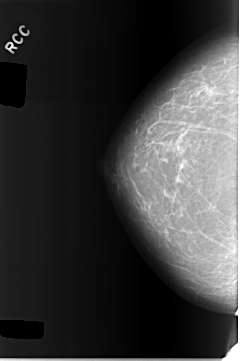

C_0301_1.LEFT_CC

FILE: C_0301_1.LEFT_CC.OVERLAY

TOTAL_ABNORMALITIES 1

ABNORMALITY 1

LESION_TYPE CALCIFICATION TYPE PLEOMORPHIC DISTRIBUTION CLUSTERED

ASSESSMENT 4

SUBTLETY 4

PATHOLOGY BENIGN

TOTAL_OUTLINES 1

BOUNDARY